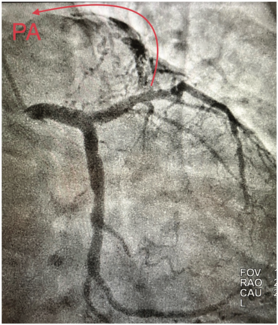

A difficult-to-cross coronary lesion, due to vessel tortuosity and almost complete occlusion, was crossed using the wire surfing technique. This case report captures the details of the case and presents it in the light of fluid hemodynamics,...